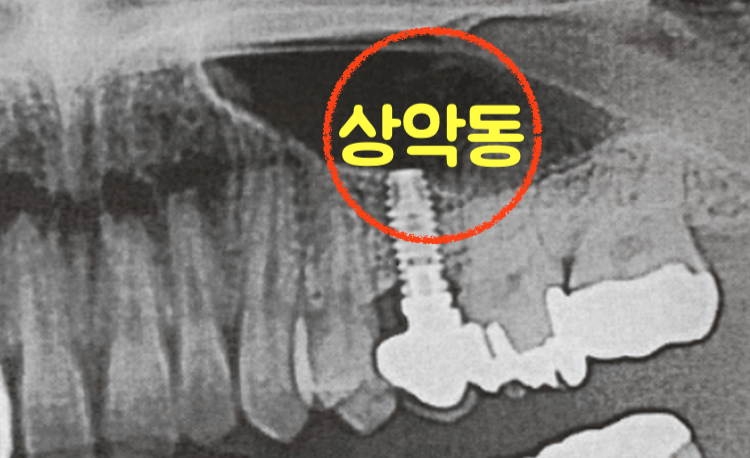

임플란트로 윗 어금니를 삽입할때 상악동 거상술 수술을 받아야 하는 경우가 있습니다. 상악동 위치 아래에 있는 어금니 같은 경우 이러한 수술을 해야하며, 상악동 거상술 통증 과 비용에 대한 정보를 직접 보험 청구 하면서 해본 후기를 남겨봅니다.

일반적으로 윗쪽 어금니를 임플란트 삽입하기 위해 상악동 거상술을 실시하며, 이러한 상악동은 광대뼈에서 윗턱뼈까지 이어진 뼈속의 빈공간을 말합니다.

위처럼 빈공간이 있으면 임플란트 삽입시 확실한 고정을 시키기 위한 뼈가 부족하기 때문에 상악동 거상술 수술을 하게 되고 이때 뼈이식을 함께 진행하여 부족한 뼈를 보충하여 임플란트를 하는 수술이라고 보면 될듯합니다.